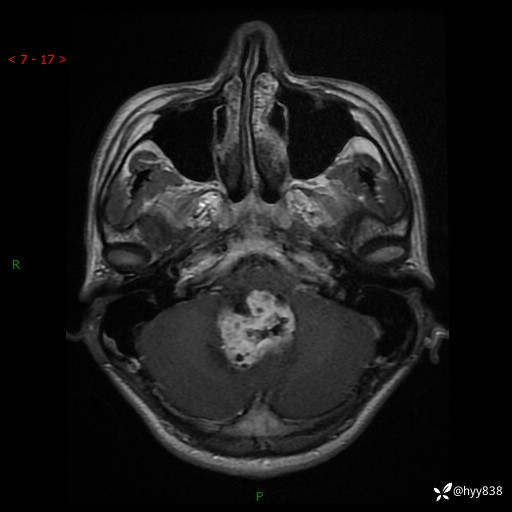

性别:男

年龄:17岁

简要病史:头痛伴间断性呕吐1月余,外院CT提示颅脑占位

颅脑MRI平扫+增强